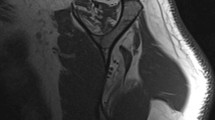

The lower trapezius tendon transfer with Achilles tendon allograft augmentation is indicated for massive irreparable posterosuperior rotator cuff tears and for paralytic shoulders lacking active external rotation (Fig. 1).

Achilles tendon allograft augmentation is required in all cases of irreparable rotator cuff tears owing to the short excursion of the lower trapezius tendon (Figs. 2 and 3). Augmentation, however, is not indicated in all cases of shoulder paralysis as long as the integrity and caliber of the infraspinatus tendon are adequate.